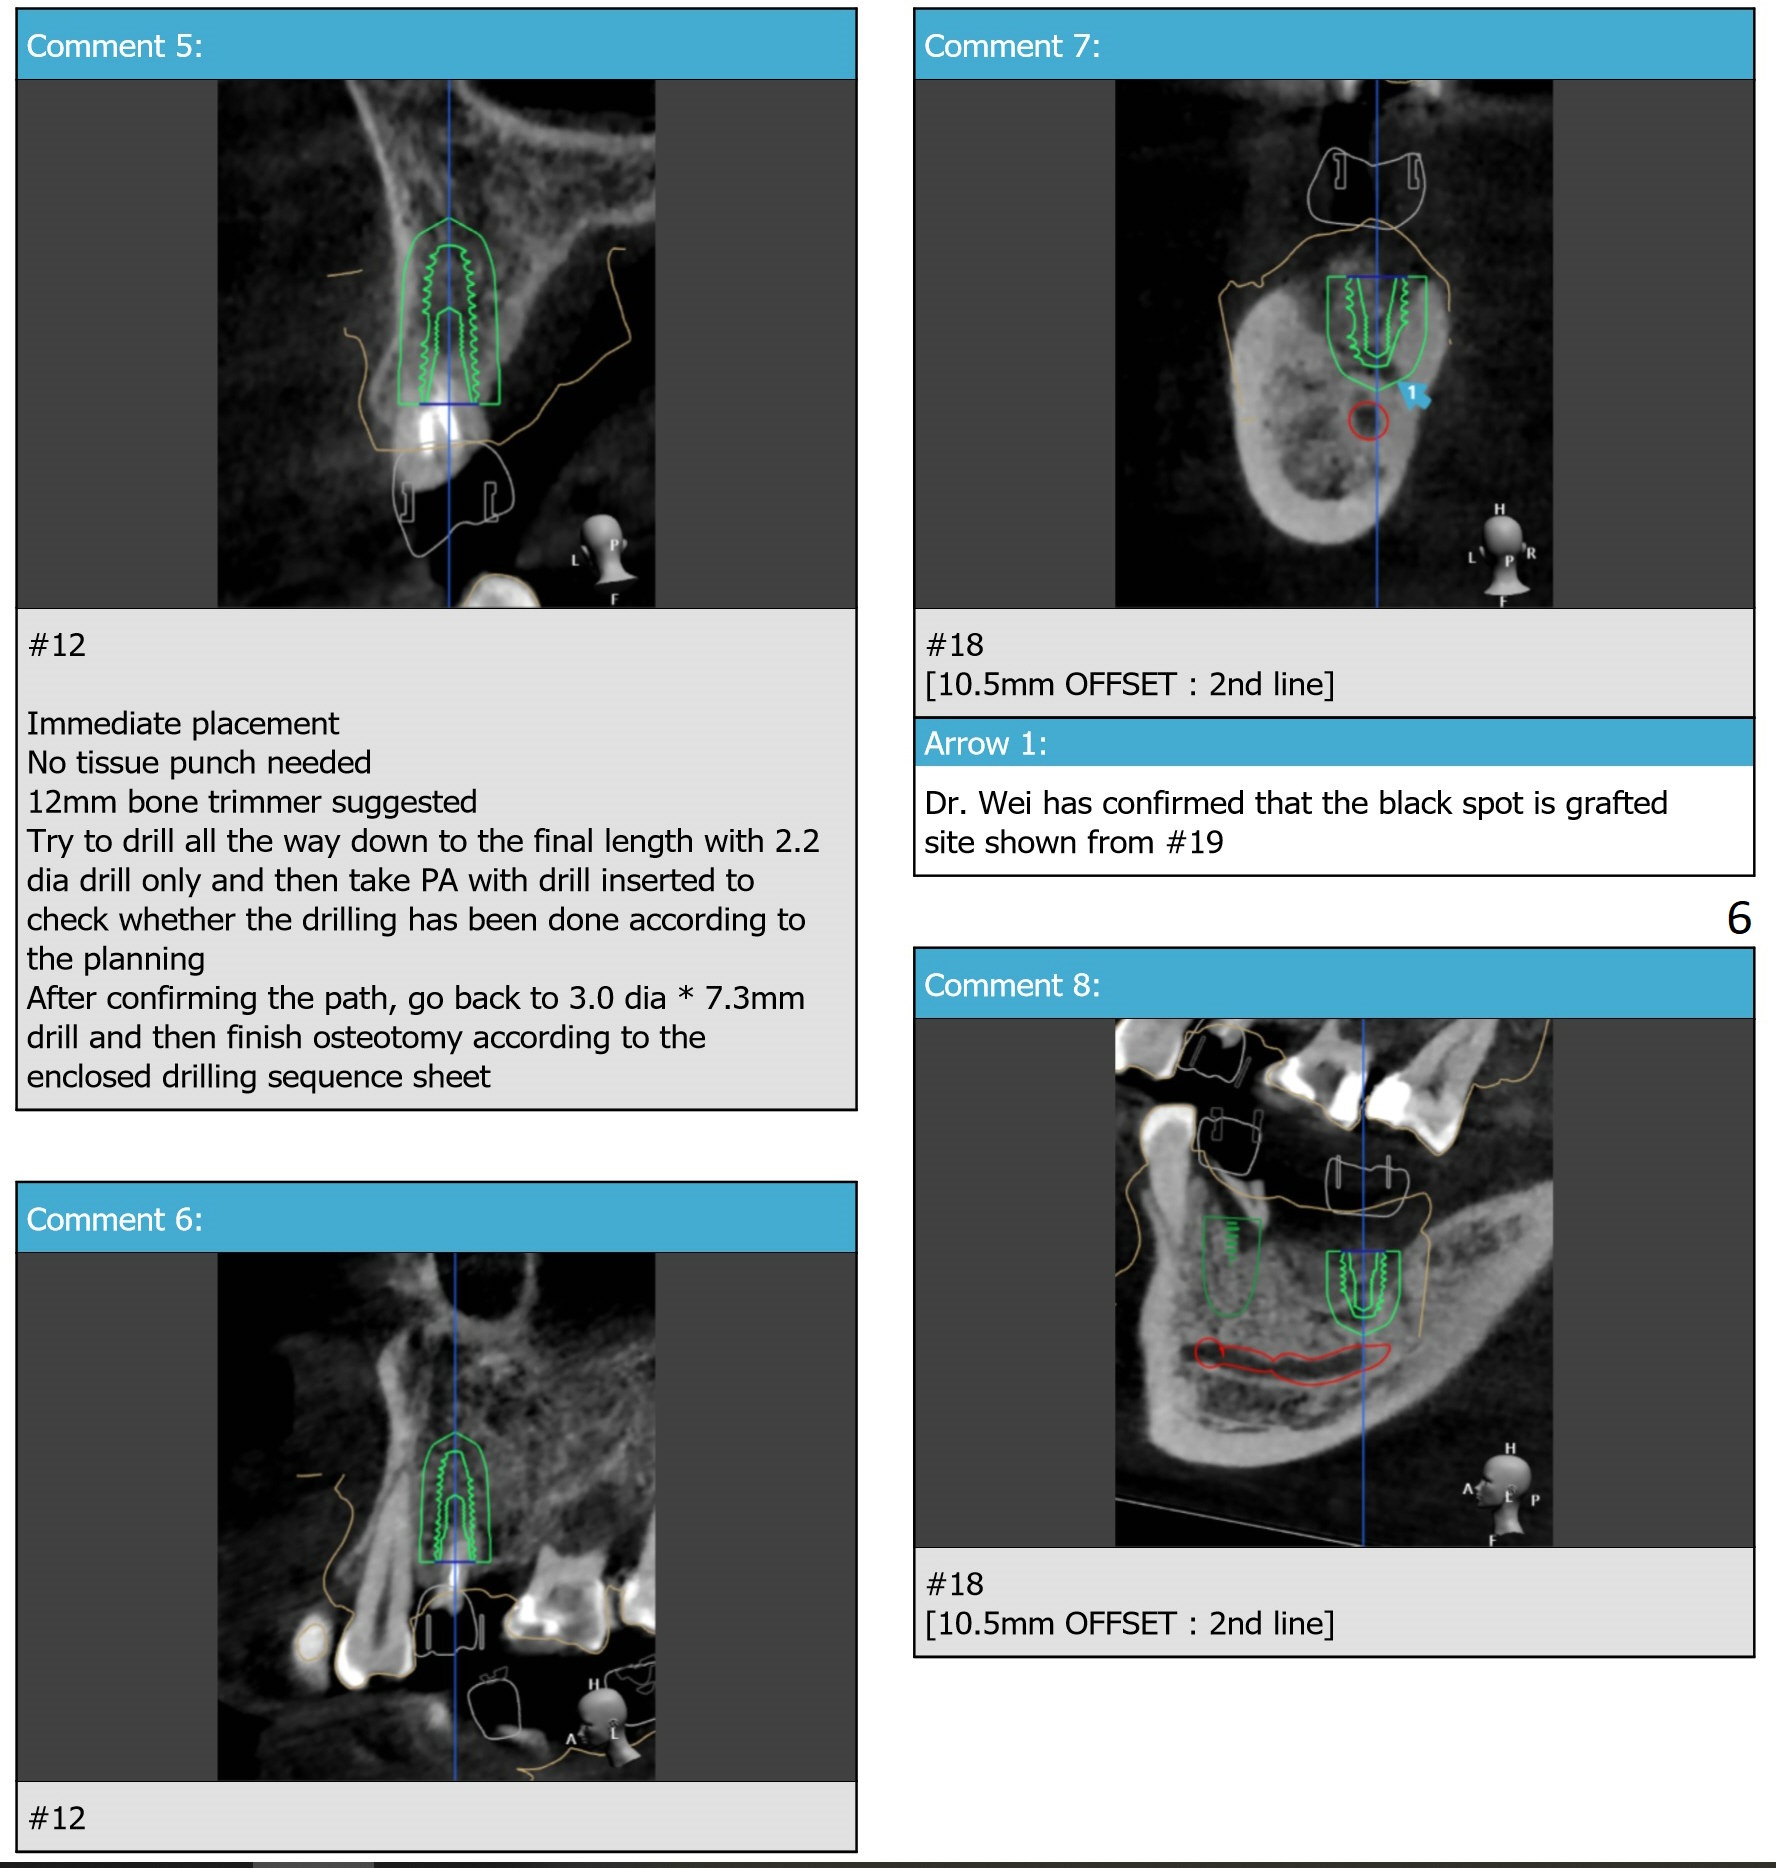

Return to Upper Premolar Lower Molar Premolar Immediate Implant, Trajectory, No Antibiotic